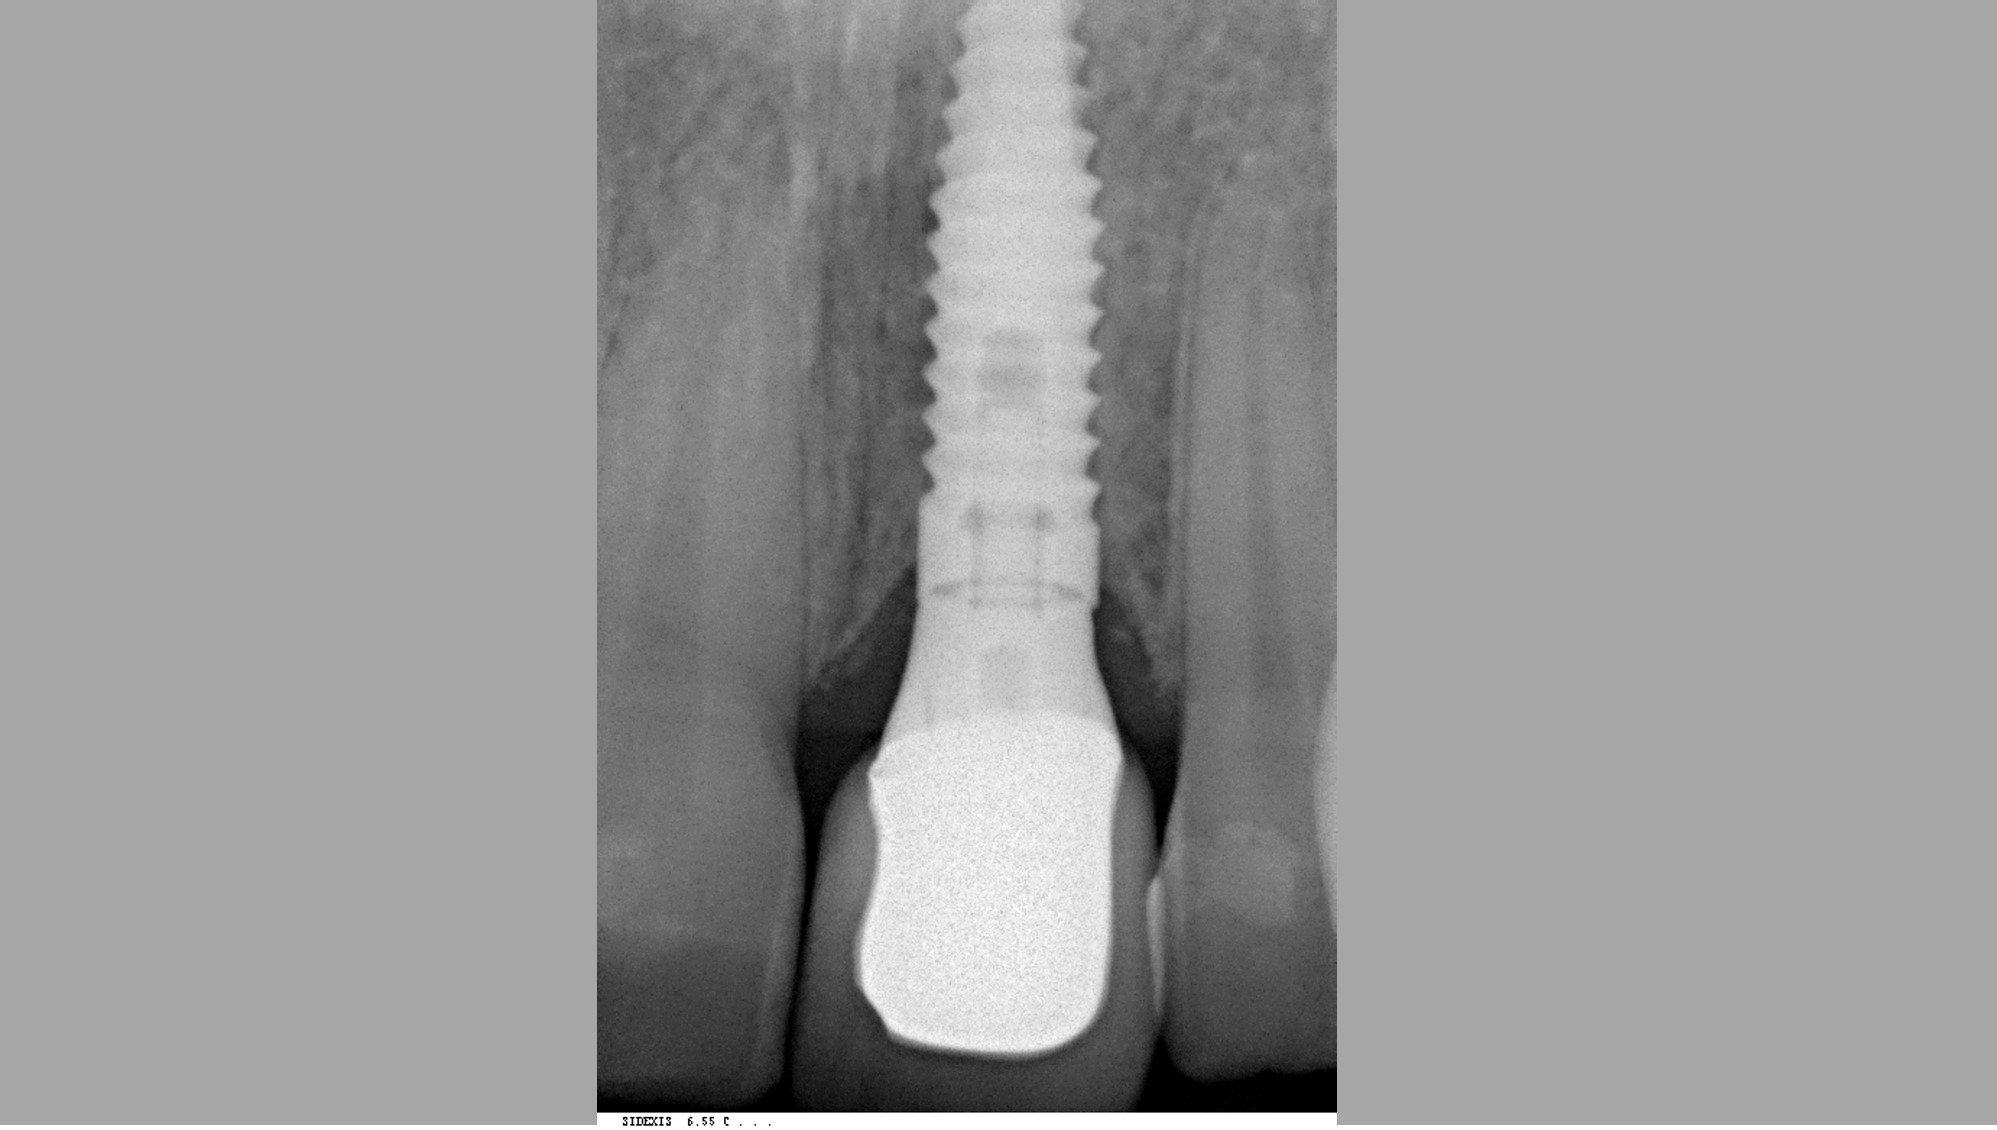

10/12 - Placement of abutment 6 months post-OPTreatment of dehiscence defect with cerabone® & Jason® membrane - Dr. M. Steigmann

12/12 - Radiographic control five years post-operativeTreatment of dehiscence defect with cerabone® & Jason® membrane - Dr. M. Steigmann